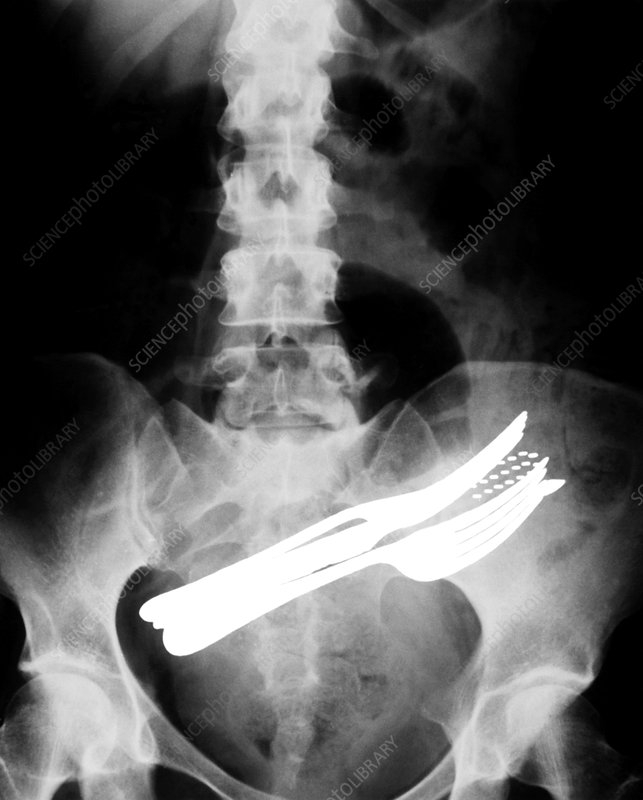

Buenas a todos, pues veréis muchas veces acabo inconscientemente con la pua en la boca, y pienso.. algún día sin darme cuenta me la trago.

Alguno le ha pasado, y si esta vivo puede contarlo?